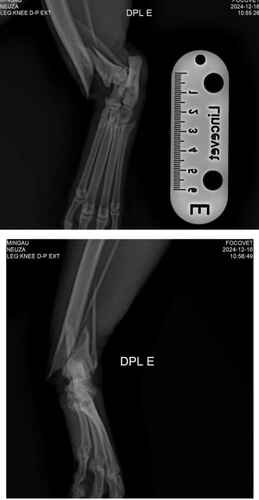

Ola, me chamo william estou criando essa vakinha para ajudar nos custos da cirurgia do mingau.Mingau é um gato que mora na rua e todos cuidam dele, mas nessa sexta feira dia 13/12 ele foi atropelado quebrou dois lugares na pata e passou por cirurgia hoje (16/12) e o custo da cirurgia ficou no valor de 1500 reais.infelizmente não temos esse dinheiro para estar pagando, já demos um abrigo para ele para se recuperar com segurança e bem alimentado